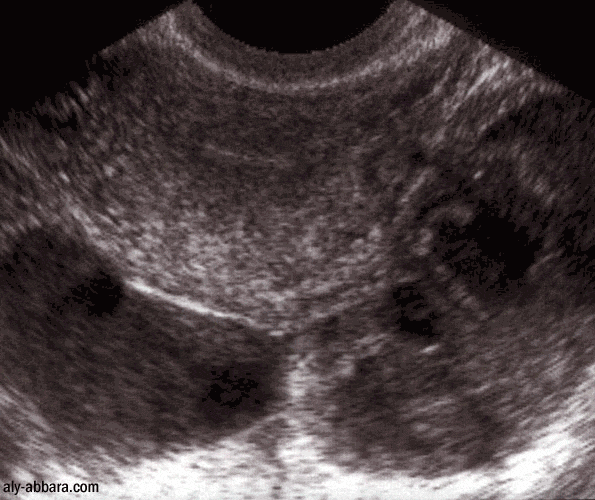

Pyosalpinx

bilatéral

Il s'agit de deux trompes infectées avec la formation de deux volumineux abcès tubaires

nécessitant une prise en charge chirurgicale immédiate